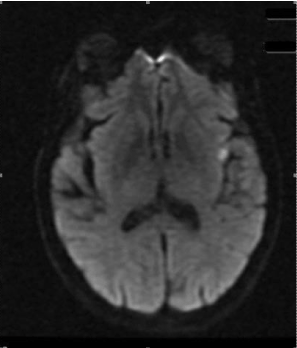

75 year old female with GD on methimazole (MMI) for two years presented to clinic. Thyroid function tests (TFTs) kept fluctuating between hypo and hyperthyroidism (TSH ranged from less than 0.01 - 51 uU/mL) on MMI and dose was adjusted every 1-2 months. On presentation, TSH was 0.109 uU/mL (0.270-4.200 uU/mL), free T4 1.78 ng/dl (0.90-1.70 ng/dl), and free T3 3.52 pg/ml (2.00-4.40 pg/ml). Thyroid stimulating immunoglobulin 493% (< 122%) was high. Thyroid uptake scan showed increased homogenous uptake of 66% and 68.4% at 3 and 25 hours, respectively. Because of difficulty controlling hormone levels, she was offered RAI therapy and received 15 millicuries. She restarted MMI 30 mg daily next day post RAI after holding it for 5 days before treatment and continued propranolol twice daily. Three days post RAI treatment; she presented to ER with right sided facial droop, slurred speech and was tachycardic with irregularly irregular pulse, right facial weakness with flattening of right nasolabial fold. Routine blood work was unremarkable. TFTs were consistent with post RAI thyrotoxicosis with TSH 0.090 uU/mL, free T4 2.42 ng/dl, free T3 6.08 pg/ml. CT scan of head was negative. MRI Brain showed acute infarction in the left insular lobe (Figure 1). Electrocardiogram showed atrial fibrillation (AF). Echocardiogram showed mild concentric hypertrophy with left ventricular ejection fraction 40%. NIH stroke scale was 4 and despite patient been in window period, tissue Plasminogen activator was not administered due to history of melena and guaiac positive stool. She was treated with apixaban, rosuvastatin and sotalol. There were no obvious other risk factors for AF and stroke. She was diagnosed with acute stroke due to cardioembolic phenomenon in the setting of post RAI thyrotoxic exacerbation and discharged home with speech therapy, neurology and endocrine follow up. Dysarthria gradually improved and was slowly tapered off MMI. Six weeks later, TFT were TSH 31.04 uU/mL and free T4 0.78 ng/dl, and started on levothyroxine.

Figure 1. Acute infarction in left insular lobe.